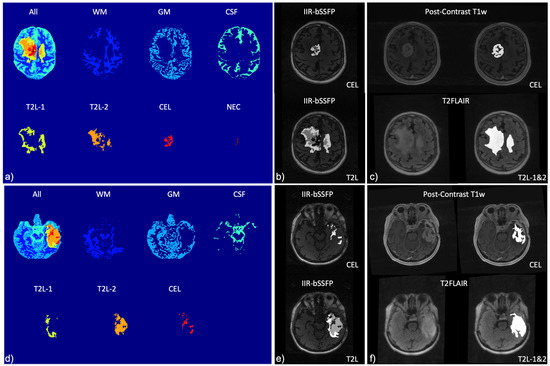

| Mapping | WM | GM | T2L-1 | T2L-2 | CEL | NEC |

|---|---|---|---|---|---|---|

| 2D T1 (ms) | 1186.4 ± 110.5 | 1589.5 ± 331.7 | 1451.5 ± 317 | 1657.9 ± 409.3 | 1947.8 ± 465.6 | 2022.3 ± 459.3 |

| 2D T2 (ms) | 90.4 ± 2.7 | 117.5 ± 12.8 | 114.7 ± 14.2 | 138.2 ± 21.3 | 153.4 ± 47.6 | 152.0 ± 41.1 |

| 3D MWF (%) | 30.4 ± 3.4 | 9.5 ± 3.3 | 12.5 ± 9.3 | 2.3 ± 1.8 | 0.55 ± 0.4 | 0.15 ± 0.0 |

| IIR-bSSFP T1 (ms) | 797.5 ± 88.3 | 670.4 ± 60.2 | 610.9 ± 58.1 | 598.4 ± 77.8 | 958.8 ± 204.9 | 1876.7 ± 608.8 |

| IIR-bSSFP T2 (ms) | 22.0 ± 5.7 | 85.2 ± 8.8 | 62.9 ± 26.5 | 115.4 ± 11.2 | 121.5 ± 10.1 | 157.5 ± 42.0 |

| IIR-bSSFP MF (%) | 14.9 ± 2.5 | 8.7 ± 1.9 | 11.9 ± 3.8 | 5.5 ± 2.6 | 3.6 ± 2.0 | 1.6 ± 0.5 |

| Mapping | CSF | WM | GM | T2L-1 | T2L-2 | CEL | NEC |

|---|---|---|---|---|---|---|---|

| IIR-bSSFP T1 (ms) | 2990.4 ± 277.4 | 848.0 ± 135.5 | 912.4 ± 218.4 | 749.5 ± 217.2 | 883.8 ± 238.8 | 1300.7 ± 303.4 | 2696.6 ± 749.7 |

| IIR-bSSFP T2 (ms) | 218.1 ± 14.9 | 28.5 ± 5.3 | 83.1 ± 20.9 | 62.2 ± 22.4 | 94.1 ± 29.1 | 115.8 ± 19.1 | 190.7 ± 31.9 |

| IIR-bSSFP MF (%) | 1.0 ± 0.4 | 10.0 ± 2.8 | 5.3 ± 1.3 | 7.8 ± 3.4 | 3.4 ± 1.3 | 2.6 ± 1.0 | 2.2 ± 1.2 |